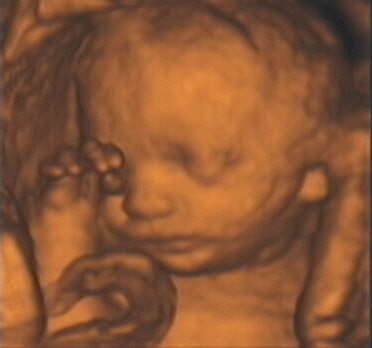

![]() |

| Figure 7, a 3-D ultrasound image of the fetus at 13 weeks gestation. Image courtesy of Stefano Ciatti, M.D. |